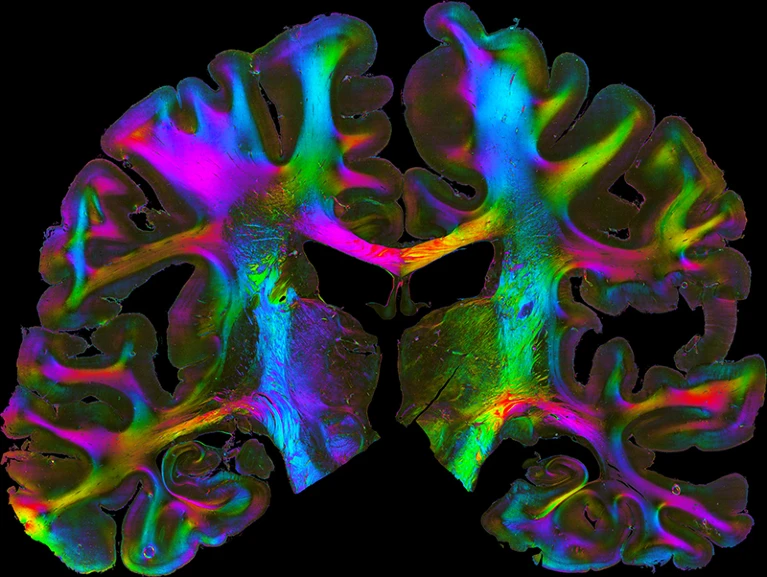

Срез человеческого мозга, демонстрирующий архитектуру волокон, соединяющих различные области.

Если не говорить об управлении, то в рамках HBP накоплен ряд важных и полезных научных данных. Создав и объединив 3D-карты около 200 структур коры головного мозга и более глубоких отделов мозга, учёные HBP создали «Атлас мозга человека», доступный через систему EBRAINS. Атлас отображает многоуровневую организацию мозга, начиная с его клеточной и молекулярной архитектуры и заканчивая функциональными модулями и связностью.

“Атлас мозга человека – это что-то вроде Google Maps, только для мозга”, – сказал Амунтс на пресс-брифинге в рамках HBP Summit 2023 в марте.

В атласе используются данные посмертного исследования мозга для создания стандартных карт, учитывающих естественные различия между людьми. Используя атлас, учёные HBP выявили шесть ранее неизвестных областей мозга в префронтальной коре, которые участвуют в развитии памяти, языка, внимания и обработки музыки. Кроме того, атлас связывает свои карты с данными об экспрессии генов, содержащимися в Allen Human Brain Atlas – базе данных, разработанной Алленовским институтом науки о мозге в Сиэтле (штат Вашингтон) и описывающей нейроны всего мозга. Используя парные атласы, исследователи выяснили, как изменения в экспрессии генов, связанные с депрессией, связаны со структурными и функциональными изменениями в одной из областей лобной коры головного мозга.

Исследователи HBP также разработали уникальные алгоритмы, позволяющие строить полномасштабные модели участков мозга на основе микроскопических изображений. С помощью этого инструмента учёные составили подробную карту области CA1 гиппокампа, важной для памяти. Карта содержит около 5 млн нейронов и 40 млрд синапсов.

В рамках HBP была детально изучена анатомия человеческого мозга и разработаны инструменты, позволяющие связать структуру и функции мозга с экспрессией генов.